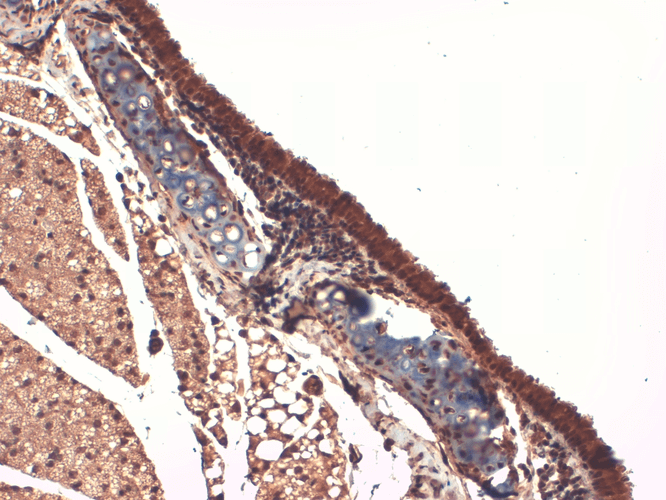

Immunohistochemistry analysis using Mouse Anti-Sodium Iodide Symporter Monoclonal Antibody, Clone 14F (11562). Tissue: Thyroid. Species: Mouse. Fixation: 10% Formalin Solution for 12-24 hours at RT. Primary Antibody: Mouse Anti-Sodium Iodide Symporter Monoclonal Antibody (11562) at 1:1000 for 1 hour at RT. Secondary Antibody: HRP/DAB Detection System: Biotinylated Goat Anti-Mouse, Streptavidin Peroxidase, DAB Chromogen (brown) for 30 minutes at RT. Counterstain: Mayer Hematoxylin (purple/blue) nuclear stain at 250-500 µl for 5 minutes at RT.

Immunohistochemistry analysis using Mouse Anti-Sodium Iodide Symporter Monoclonal Antibody, Clone 14F (11562). Tissue: Trachea. Species: Mouse. Fixation: 10% Formalin Solution for 12-24 hours at RT. Primary Antibody: Mouse Anti-Sodium Iodide Symporter Monoclonal Antibody (11562) at 1:1000 for 1 hour at RT. Secondary Antibody: HRP/DAB Detection System: Biotinylated Goat Anti-Mouse, Streptavidin Peroxidase, DAB Chromogen (brown) for 30 minutes at RT. Counterstain: Mayer Hematoxylin (purple/blue) nuclear stain at 250-500 µl for 5 minutes at RT. - -